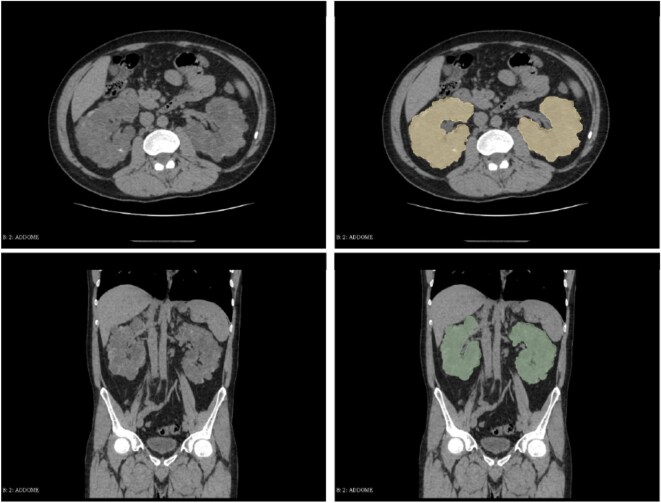

Methods: We retrospectively selected a cohort of 58 ADPKD patients who routinely underwent CT scan for total kidney volume (TKV) assessment from February 2020 to March 2021. An expert radiologist generated a region-of-interest segmentation for cystic kidneys from which we extracted 217 radiomic features. In a subgroup of 51 patients with at least three serum creatinine measurements, on the basis of estimated glomerular filtration rate we identified 26 rapid progressors to ESKD (>3 mL/min/1.73 m2/year), and we developed a radiomic model to discriminate rapid from non-rapid progressors. Area under the curve (AUC) of the receiver operating characteristic (ROC) and sensitivity were employed to evaluate models' performance.